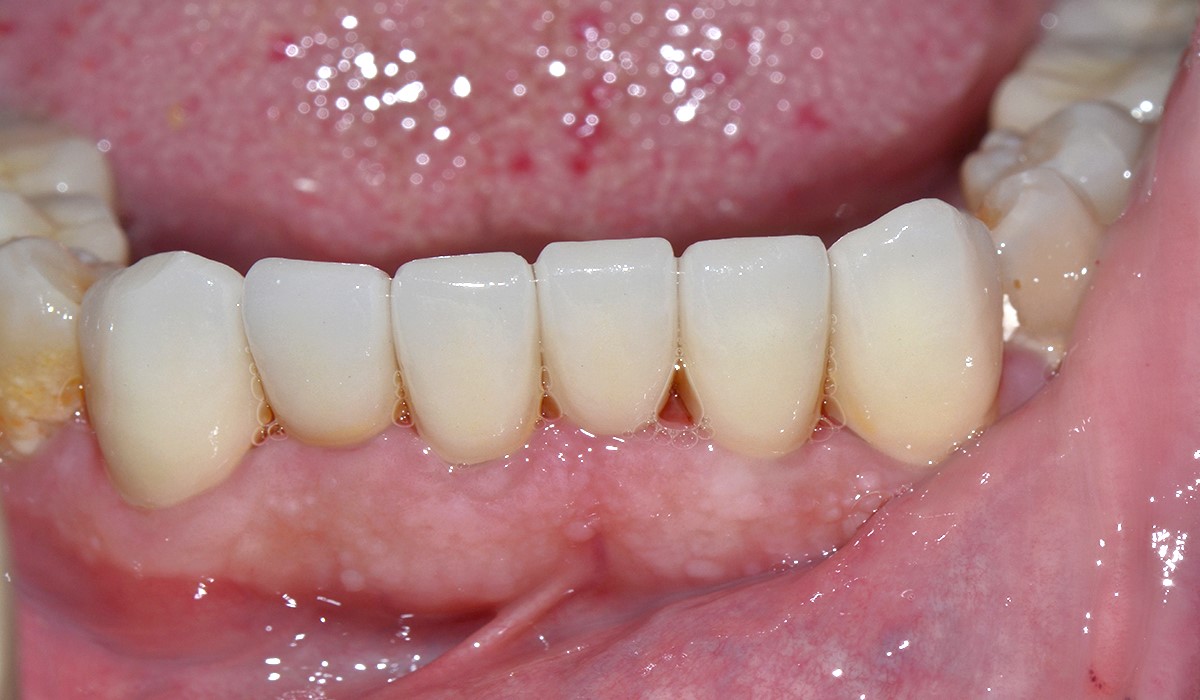

Patient avec des chevauchements dentaires favorisant l’apparition de tartre. Des facettes céramique sont réalisées de manière à rétablir une implantation correcte des incisives inférieures.